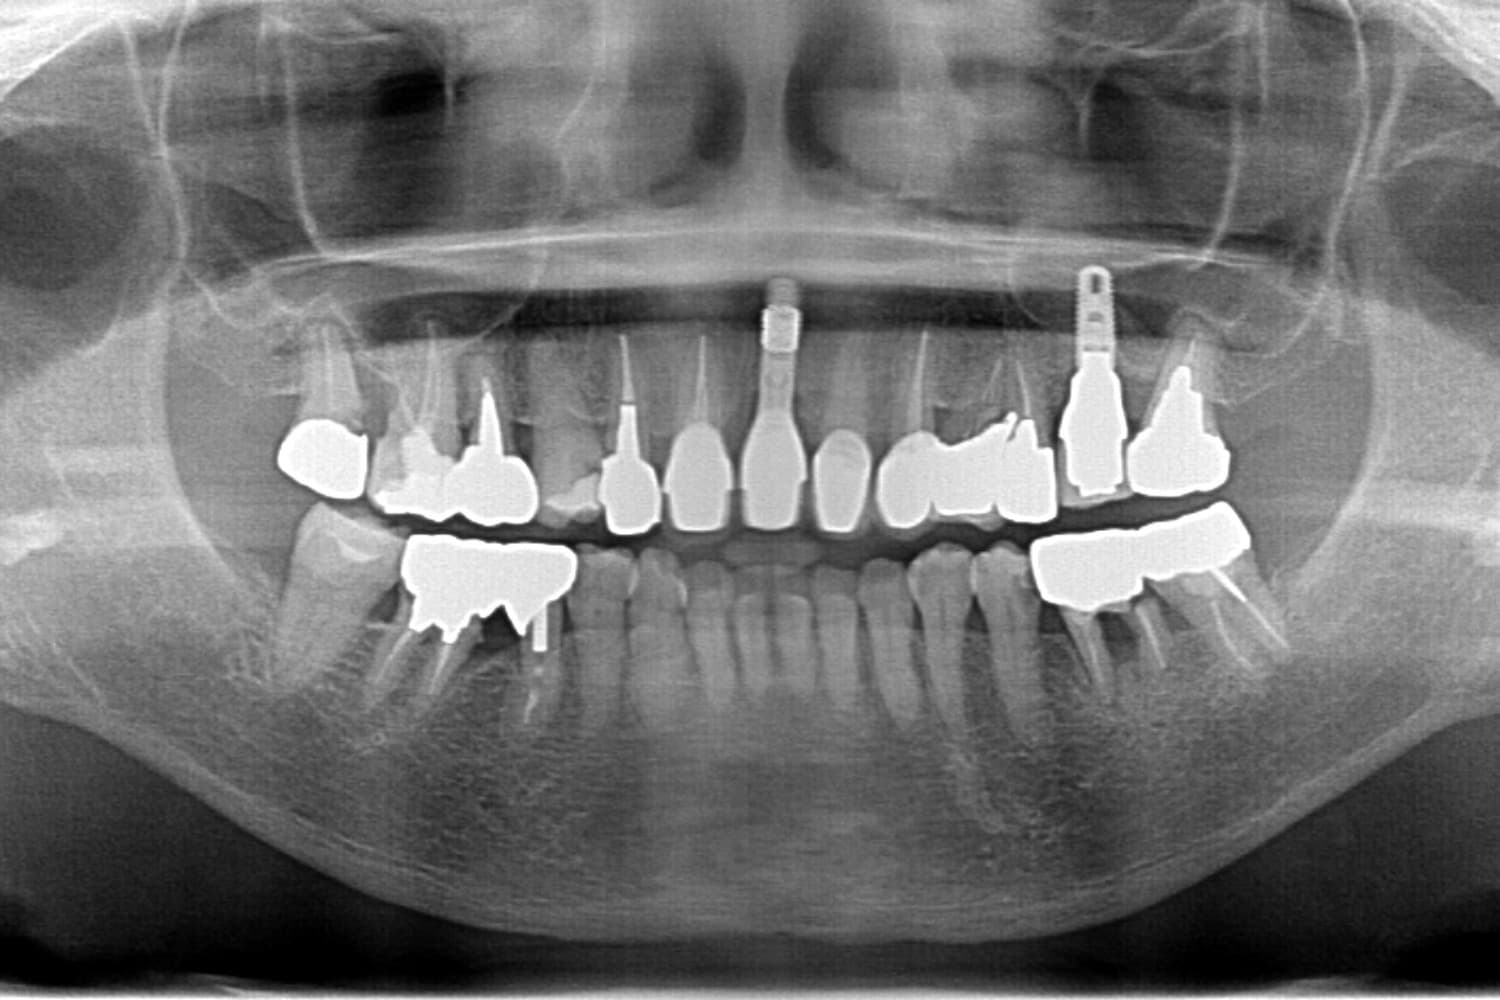

After

オールオン4

10カ月

12回

6,000,000円+骨造成代

メインテナンスが出来ていないとインプラント周囲炎になる。よく噛めるため、上部構造が使用していくうちに破損することがある。